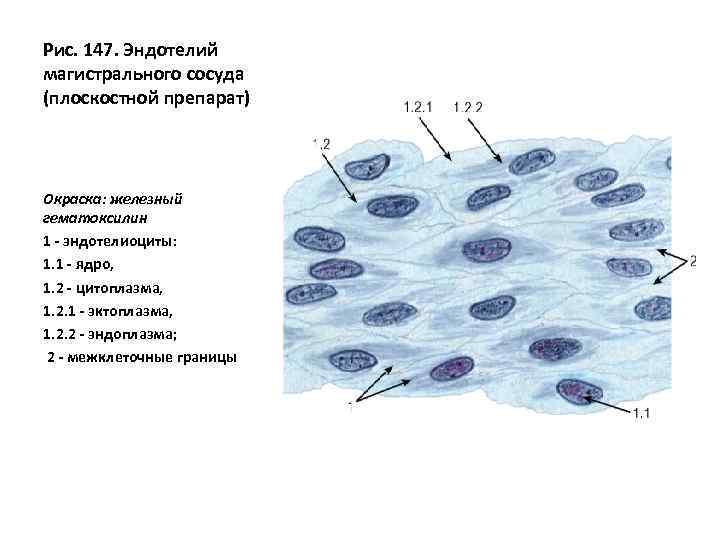

Структура клеток: Эктоплазма и цитоплазма в научных изображениях